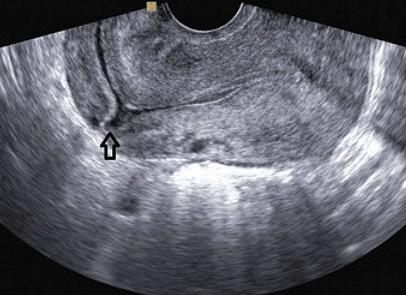

УЗИ матки проводят обычно на вторые или третьи сутки после рождения ребенка. Для этого применяется трансабдоминальный способ диагностики. Это означает, что врач проводит обследование через брюшную стенку. Выбор трансабдоминального обследования определяется тем, что величина матки в этот период еще достаточно крупная, и врач не сможет полностью обследовать ее с помощью вагинального датчика.

Влагалищное обследование проводится только для детального обследования состояния шейки матки. В обязательном порядке специалист должен проанализировать состояние полости матки после рождения.

Трансвагинальное обследование позволяет более подробно изучить состояние шейки матки, однако, такой способ используется довольно редко из-за сложности выполнения процедуры в послеродовой период

Норма УЗИ говорит о том, что полость может быть незначительно расширена, так как в ней визуализируется небольшое количество сгустков. На вторые – третьи сутки они локализованы в верхней части, а затем перемещаются в ее нижнюю часть.

Когда состояние рожавшей нормальное в послеродовом периоде, УЗИ назначают только ко вторым-третьим суткам. В норме используют трансабдоминальный метод. Он более удобный в послеродовом периоде. Ведь обследовать большую по размерам матку изнутри посредством влагалищного датчика довольно-таки сложно. Трансвагинальную диагностику назначает специалист в том случае, когда необходимо тщательно осмотреть шейку.

Посредством ультразвука оценивают полость матки, ее состояние. Она должна быть щелевидной, слегка расширенной. Внутри нее находится незначительное количество крови, кровяных сгустков, которые локализируются в верхней части органа. Это содержимое опуститься к низу на 5-е – 7-е сутки.